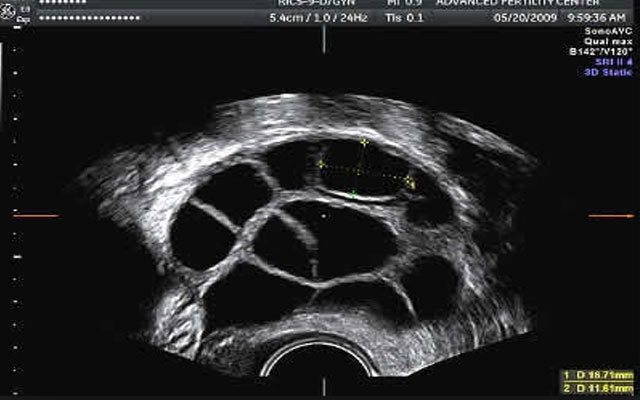

За ростом фолликулов следят с помощью УЗ-сканера, размер созревшей клетки составляет 10–13 мм. Также врач следит за уровнем гормонов, чтобы не вызвать гиперовуляцию. По результатам исследования назначается день для забора материала.

Фолликулы на мониторе УЗ-аппарата